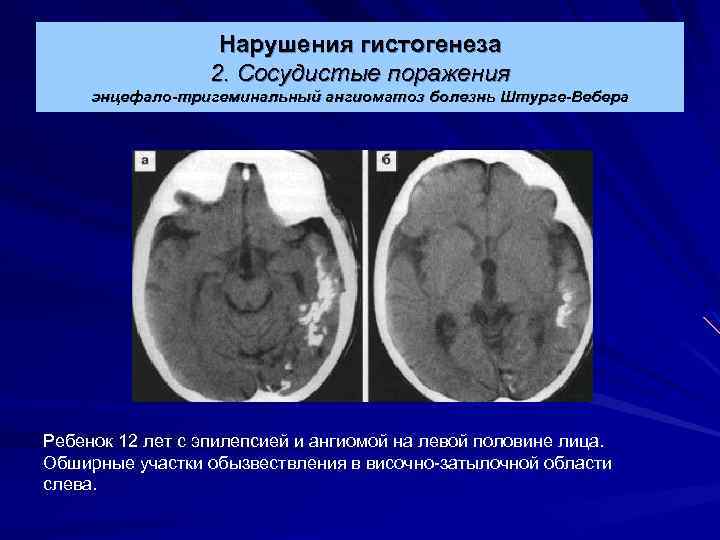

Нарушения гистогенеза 2. Сосудистые поражения энцефало-тригеминальный ангиоматоз болезнь Штурге-Вебера Ребенок 12 лет с эпилепсией и ангиомой на левой половине лица. Обширные участки обызвествления в височно-затылочной области слева.